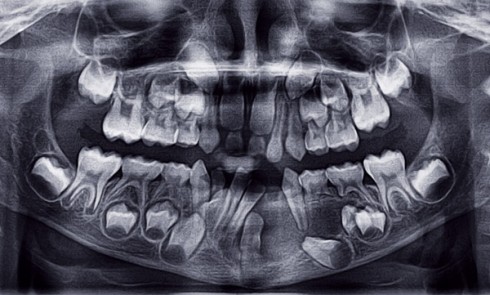

Article réservé à nos abonnés Prise en charge prothétique d’un enfant atteint d’une dysplasie ectodermique hypohidrotique

La dysplasie ectodermique est une génodermatose héréditaire liée au chromosome X qui comprend toute une série d’anomalies du développement et...